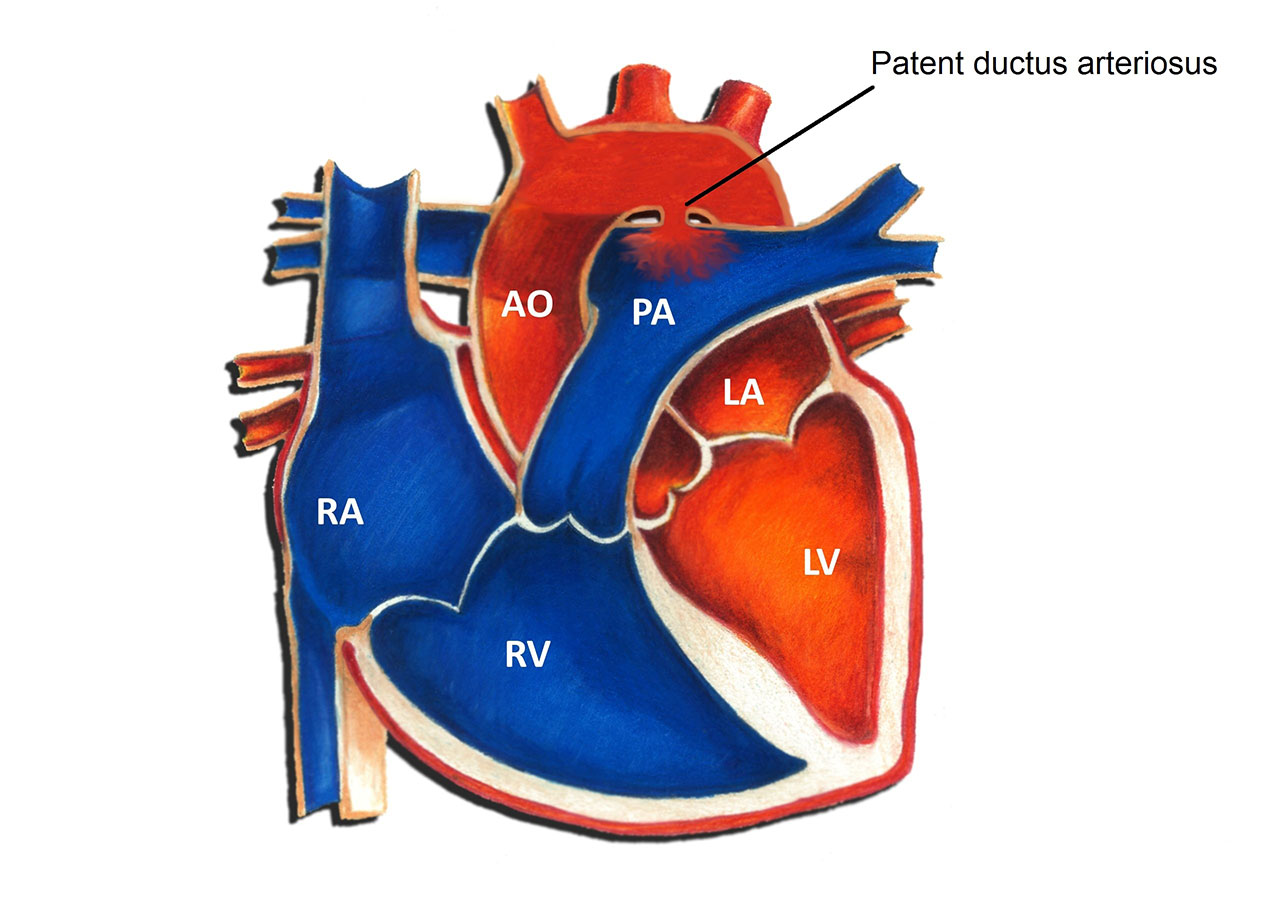

PDA Pathophysiology and Anatomy

Morphology of the PDA in premature infants The PDA resembles a hockey

What is this PDA and why do the doctors want to close it

Text Patent Ductus Arteriosus PDA in Premature Infants

PATENT DUCTUS ARTERIOSUS PDA IN CHILDREN Dr Gaurav Agrawal

What is PDA in Newborn Babies

What is PDA in Newborn Babies

A Assessment of patent ductus arteriosus PDA Image quot a quot shows PDA

Patent Ductus Arteriosus PDA in the newborn

Patent ductus arteriosus PDA in preterm infants A the

PDA morphology and size are extremely variable in premature babies